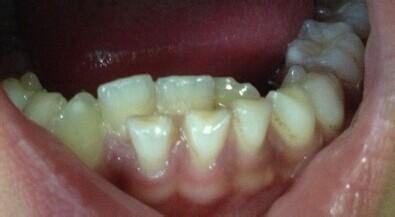

“妈妈,为什么我会像鲨鱼一样有好多牙齿?”上个月家住季华五路的王女士听到女儿说中间右下的牙齿松动,当时她不以为然,觉得女儿6岁是到换牙的时候了。万万没想到,短短半个多月的时间,乳牙还没有脱落,就有两颗恒牙在乳牙后面挤了出来。

佛山市口腔医院(佛山市牙病防治指导中心)专家介绍称,一般情况下,孩子6、7岁时,乳牙就完成使命,自动脱落,随后恒牙逐渐萌出,成为孩子一辈子否贸印的好伙伴。但是,有些孩子恒牙已经长出来了,而相应的乳牙却不肯“退位让贤”,恒牙被迫从乳牙后面“委曲求全”,从而形成一前一后两层牙齿。这时候,如果不及时把顽固的乳牙拔掉,就会影响恒牙的正常生长,导致牙齿错位,排列不齐,咬合不正。

生命在于运动,牙齿也一样。牙齿的主要作用就是咀嚼食物,宝宝长出乳牙后,让牙齿多咀嚼食物,多“锻炼”,才能促进乳牙牙根的生长发育,而到了一定时期(6、7岁)它才会自然脱落,这是符合一般自然规律的事情,类似于“瓜熟蒂落”。但是,很多家长担心宝宝吃韧性大的东西噎着,怕硬的食物损伤牙齿,把宝宝的食物都弄得过于精细,青菜切断了吃,坚果磨粉冲泡着吃,苹果削片甚至蒸熟了吃。这些精细的食物缺乏纤维,食用时根本无需过多咀嚼,不能充分给予乳牙生理性的刺激,从而让乳牙的牙根和牙槽骨的连接密不可分。恒牙无法取缔对应位置的乳牙,只能“另寻出路”,从乳牙的后方长出,这就形成了双层牙。